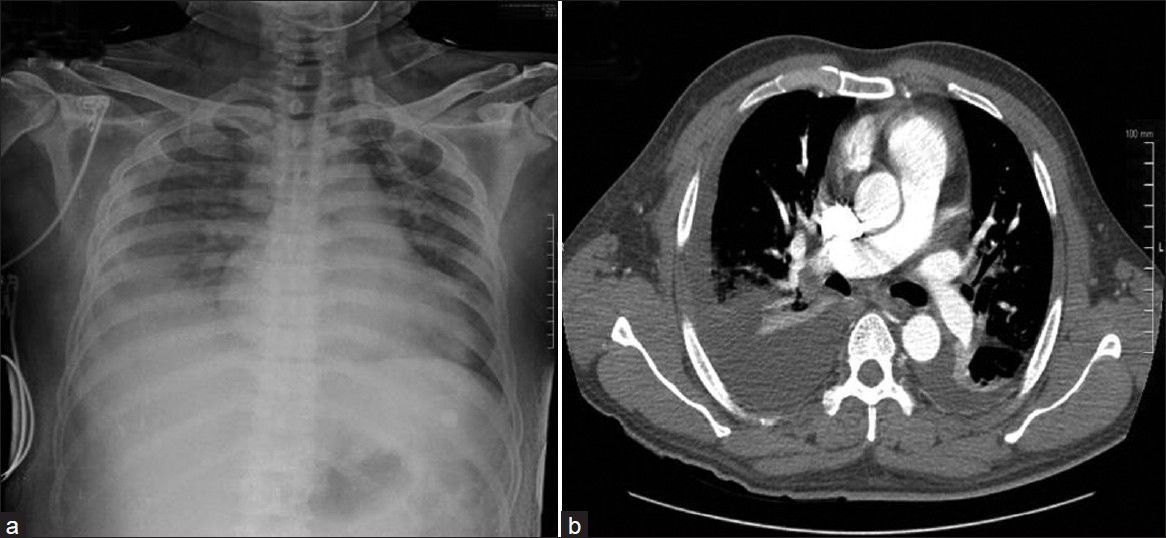

Shoshin beriberi is a type of wet beriberi that is rapid in onset and is also known as acute fulminant cardiovascular beriberi. Wet beriberi denotes thiamine deficiency that is associated with the involvement of cardiovascular system. Shoshin beriberi is a rapid type of wet beriberi that results due to injury that is majorly confined to the heart and leads to cyanosis of the extremities, tachycardia, neck vein distention, restlessness, and anxiety. Treatment is not only with thiamine alone as that results in systemic vasoconstriction without recovery of the heart and ultimate low-output cardiac failure. The treatment needs to include support for the heart along with thiamine otherwise rapid death can occur. Text Reference: https://emedicine.medscape.com/article/116930-overview#a4 Image Source: https://www.najms.org/article.asp?issn=1947-2714;year=2012;volume=4;issue=10;spage=503;epage=506;aulast=Saya